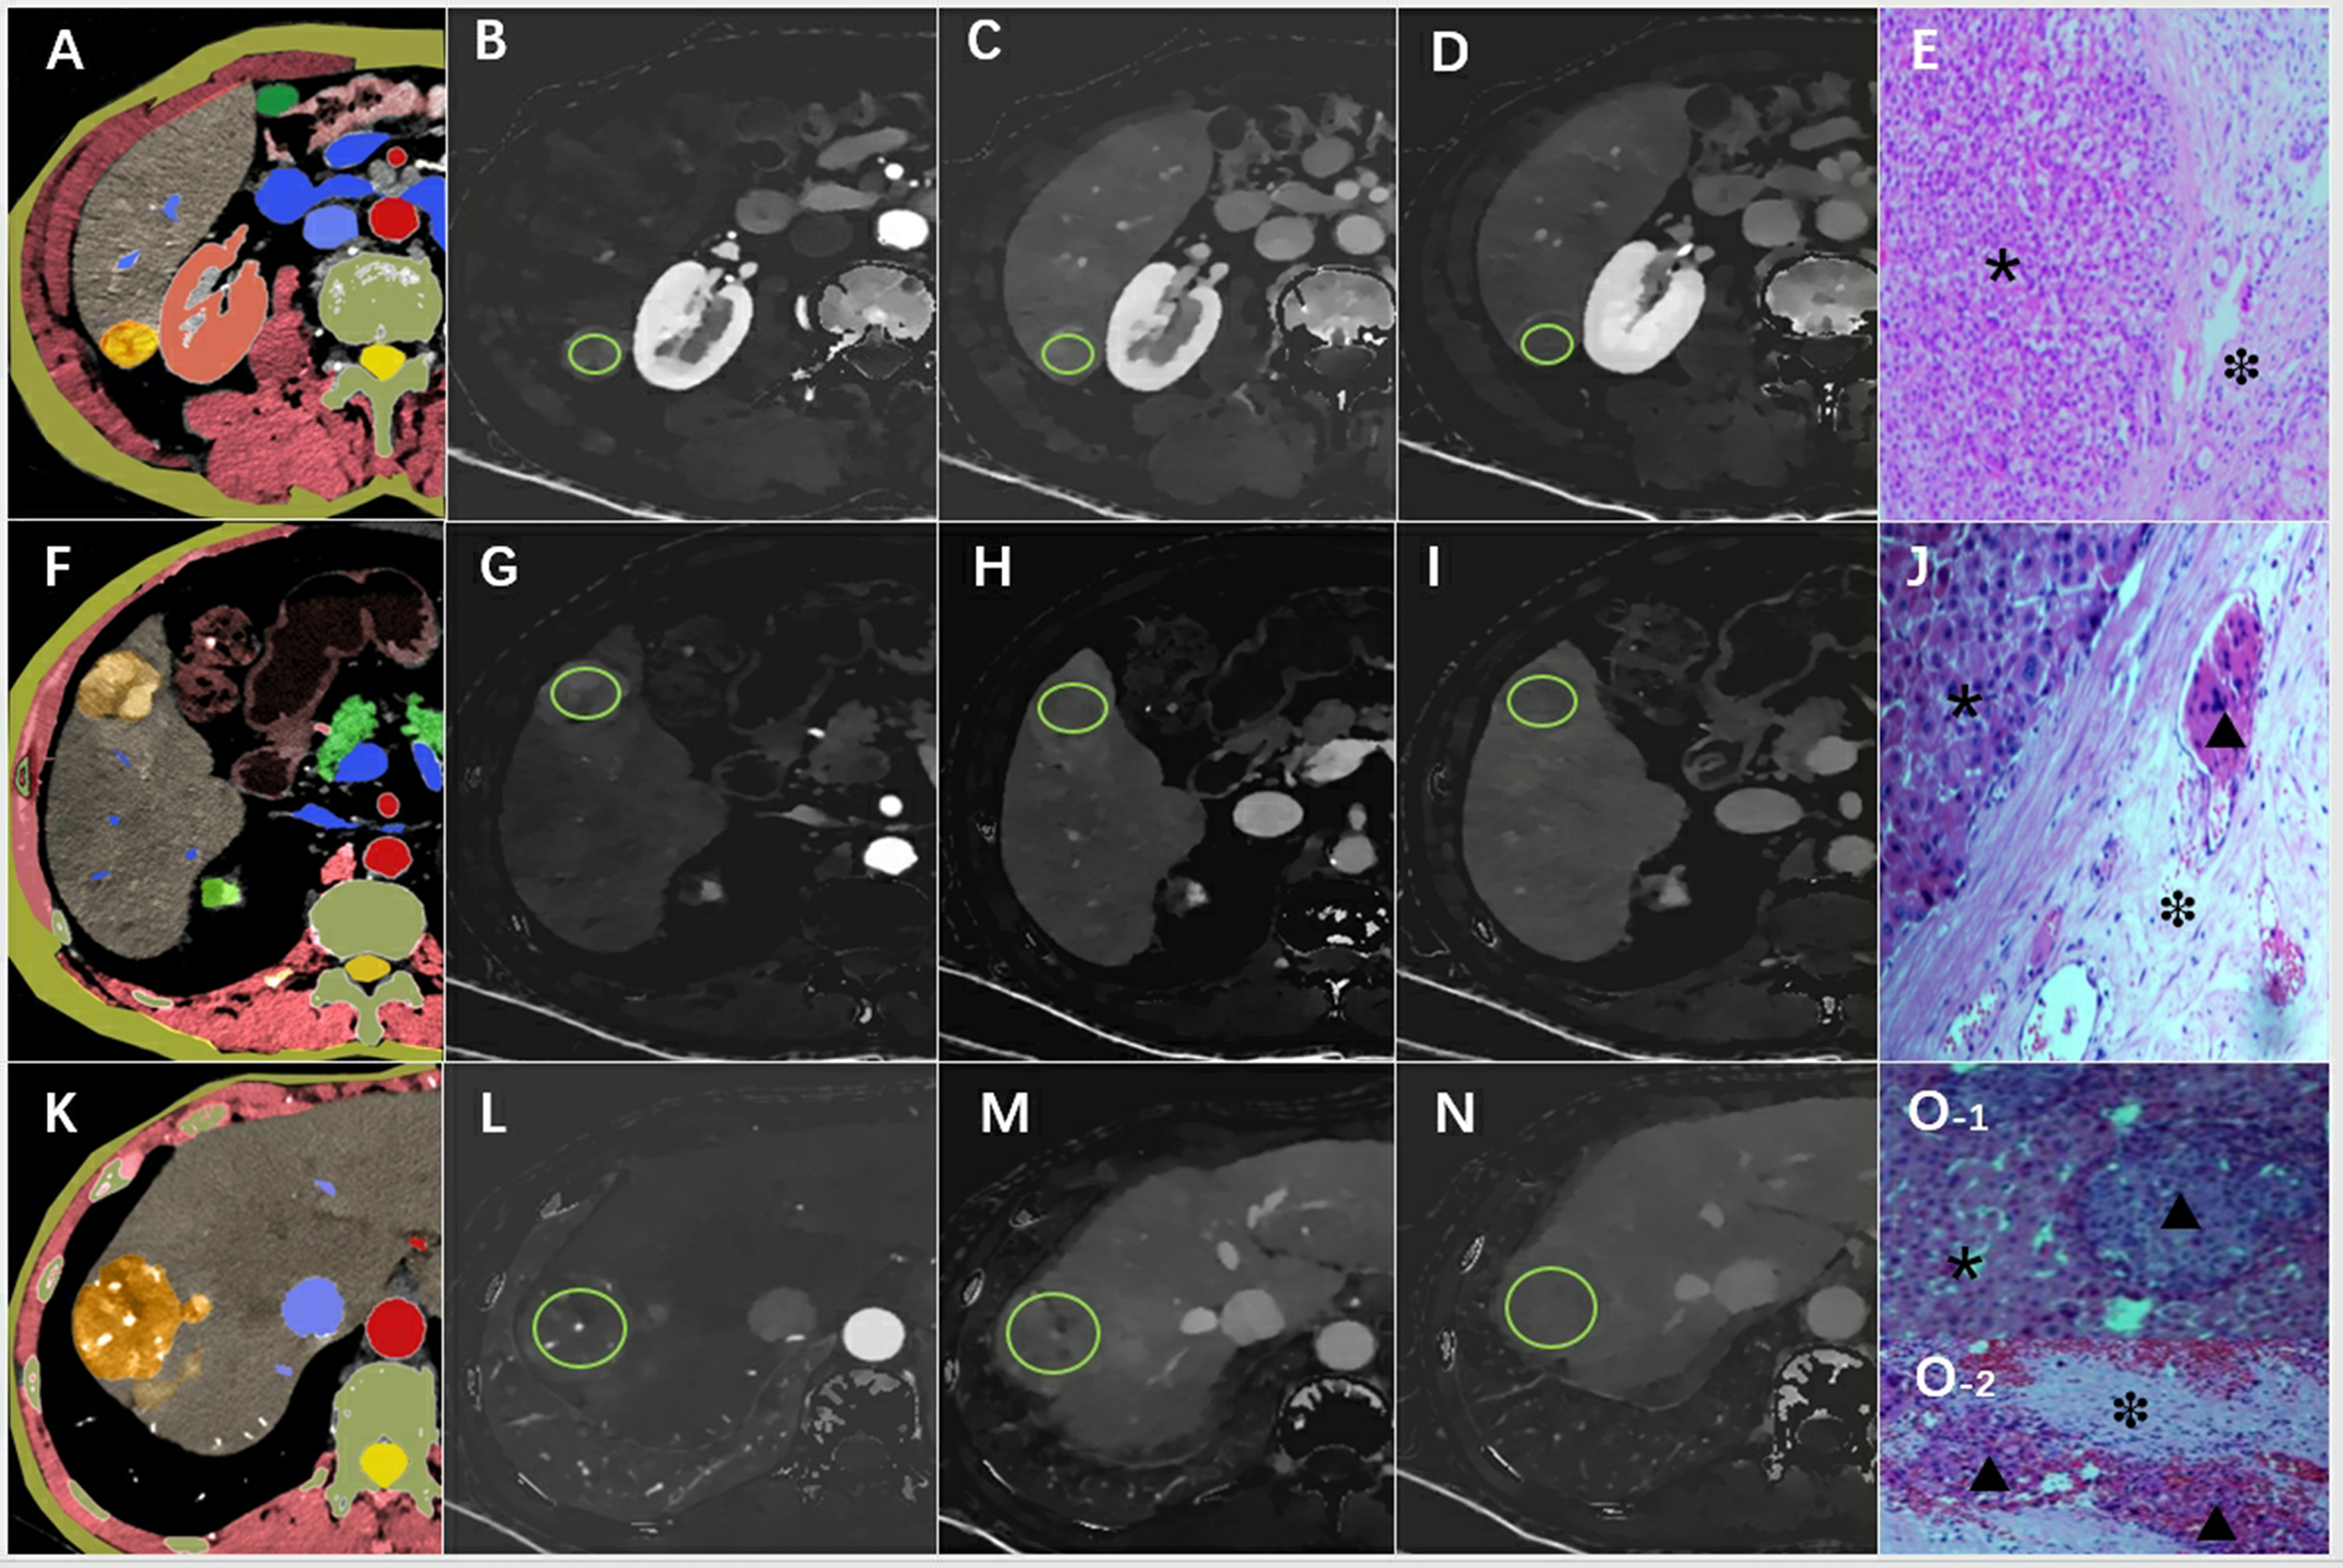

Figure 2

An example of the definition of the regions of interest. Examples of the definition of the regions of interest (ROIs) (light green circles) for quantitative analyses. (A) Schematic diagram of hepatocellular carcinoma with smooth tumor margin, (B) ID-A=1.02 mg/ml, (C) ID-P=1.23 mg/ml, (D) ID-D=1.05 mg/ml, (E) pathological pictures (×200), the tumor area (*) and MVI-negative in the normal area (❉) around the tumor were marked. (F) Schematic diagram of hepatocellular carcinoma with nodule-in-nodule architecture, (G) ID-A=1.87 mg/ml, (H) ID-P=1.58 mg/ml, (I) ID-D=1.32 mg/ml, (J) pathological pictures (×200) showed the tumor area (*) and MVI-positive(▴) in the normal area(❉) around the tumor. (K) Schematic diagram of hepatocellular carcinoma with corona enhancement, (L) ID-A=1.64 mg/ml, (M) ID-P=1.43 mg/ml, (N) ID-D=1.02 mg/ml, (O) pathological pictures (×200), O-1 shoued MVI-positive (▴) in the tumor (*), and also combined with MVI-positive (▴) in normal area (❉) in the O-2. ID-A, iodine density in hepatic arterial phase; ID-P, iodine density in portal-venous phase; ID-D, iodine density in delayed phase.